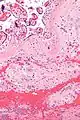

Chronic deciduitis

Chronic deciduitis is a type of long-lasting inflammation that arises in pregnancy and affects the endometrial stromal tissue (decidua).

| Micrograph of a chronic deciduitis, showing the characteristic plasma cells. H&E stain. | |

It is associated with preterm labour.[1] The diagnosis rests primarily on the presence of plasma cells.[2]

Intermed. mag.